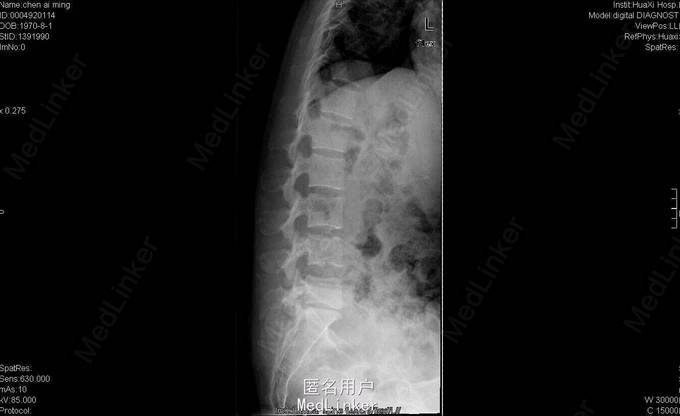

女,40岁2月,因“腰部反复疼痛2+年,加重伴双下肢疼痛、麻木1+年”入院。视:脊柱外观无畸形,皮肤未见红肿、皮疹、破溃、色斑等,无明显包块。触:腰5骶1椎棘突压痛,椎旁肌压痛,无放射痛。腰骶部感觉麻木。双下肢小腿外侧及足背感觉减退,右侧明显,其余肢体感觉正常,肌张力正常。鞍区右侧感觉减退。双下肢足背动脉搏动好。皮温正常。双膝腱减弱,踝阵挛、髌阵挛(-),巴氏征(-),右下肢直腿抬高试验(30°),直腿抬高加强试验(+),左下肢直腿抬高试验(-)。“4”字征阴性。动量:腰部不能屈伸活动,侧弯可,双下肢活动度正常,四肢肌力正常。CT及MRI:腰5骶1椎间盘脱出,腰4-5椎间盘轻度膨出,硬膜囊受压;腰5骨质增生。腰5骶1椎间盘突出症伴小关节退变。双侧椎板开窗腰5骶1椎间盘髓核摘除、内固定术。